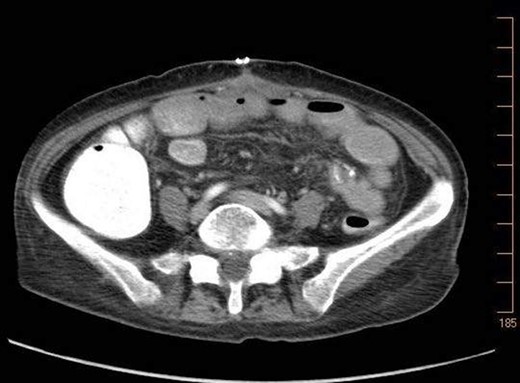

A 57-year-old non-toxic appearing female with a medical history of diverticulosis and malnutrition, and a surgical history significant for small bowel obstruction due to jejunal lymphangioma status post exploratory laparotomy and resection of bowel (2.2018). This patient presents with epigastric pain ×2 days with radiation to left upper quadrant and nausea with emesis, concerning for obstruction. In the Emergency Department, the patient was non-toxic appearing, hemodynamically stable, with no leukocytosis (7.4), or elevated lactic acid (1.2). Imaging, XR (Fig. 1) and CTAP (Fig. 2), demonstrating SBO with free air concern for perforated viscus. The concern for free air on imaging, in the setting of abdominal pain with symptoms of obstruction, mandated an operative intervention. On 7.5.18 the patient underwent exploratory laparotomy and was found to have emphysema of proximal jejunum, and underwent 125 cm resection of jejunum (Figs 3 and 4). Pathology of the specimen demonstrated multiple air filled cystic serosal nodules consistent with PCI (Figs 3 and 4, Supplementary Fig. S7).

7.4.18:CTAP w/IV and PO contrast: suggestive for small bowel obstruction, distal small bowel collapsed, mild or moderate free air suggestive of perforated viscus, free fluid in dependent portion of pelvis.